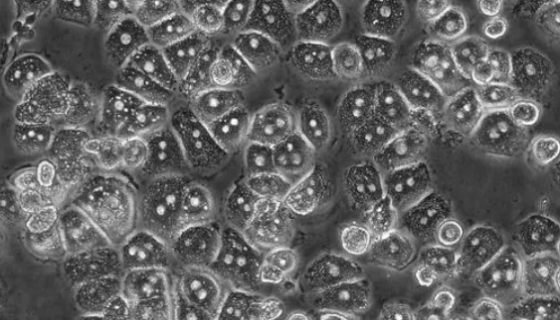

LN-18人神經膠質瘤貼壁細胞系的培養(yǎng)操作及應用!

LN-18人神經膠質瘤貼壁細胞系簡稱膠質瘤,是發(fā)生于神經外胚...